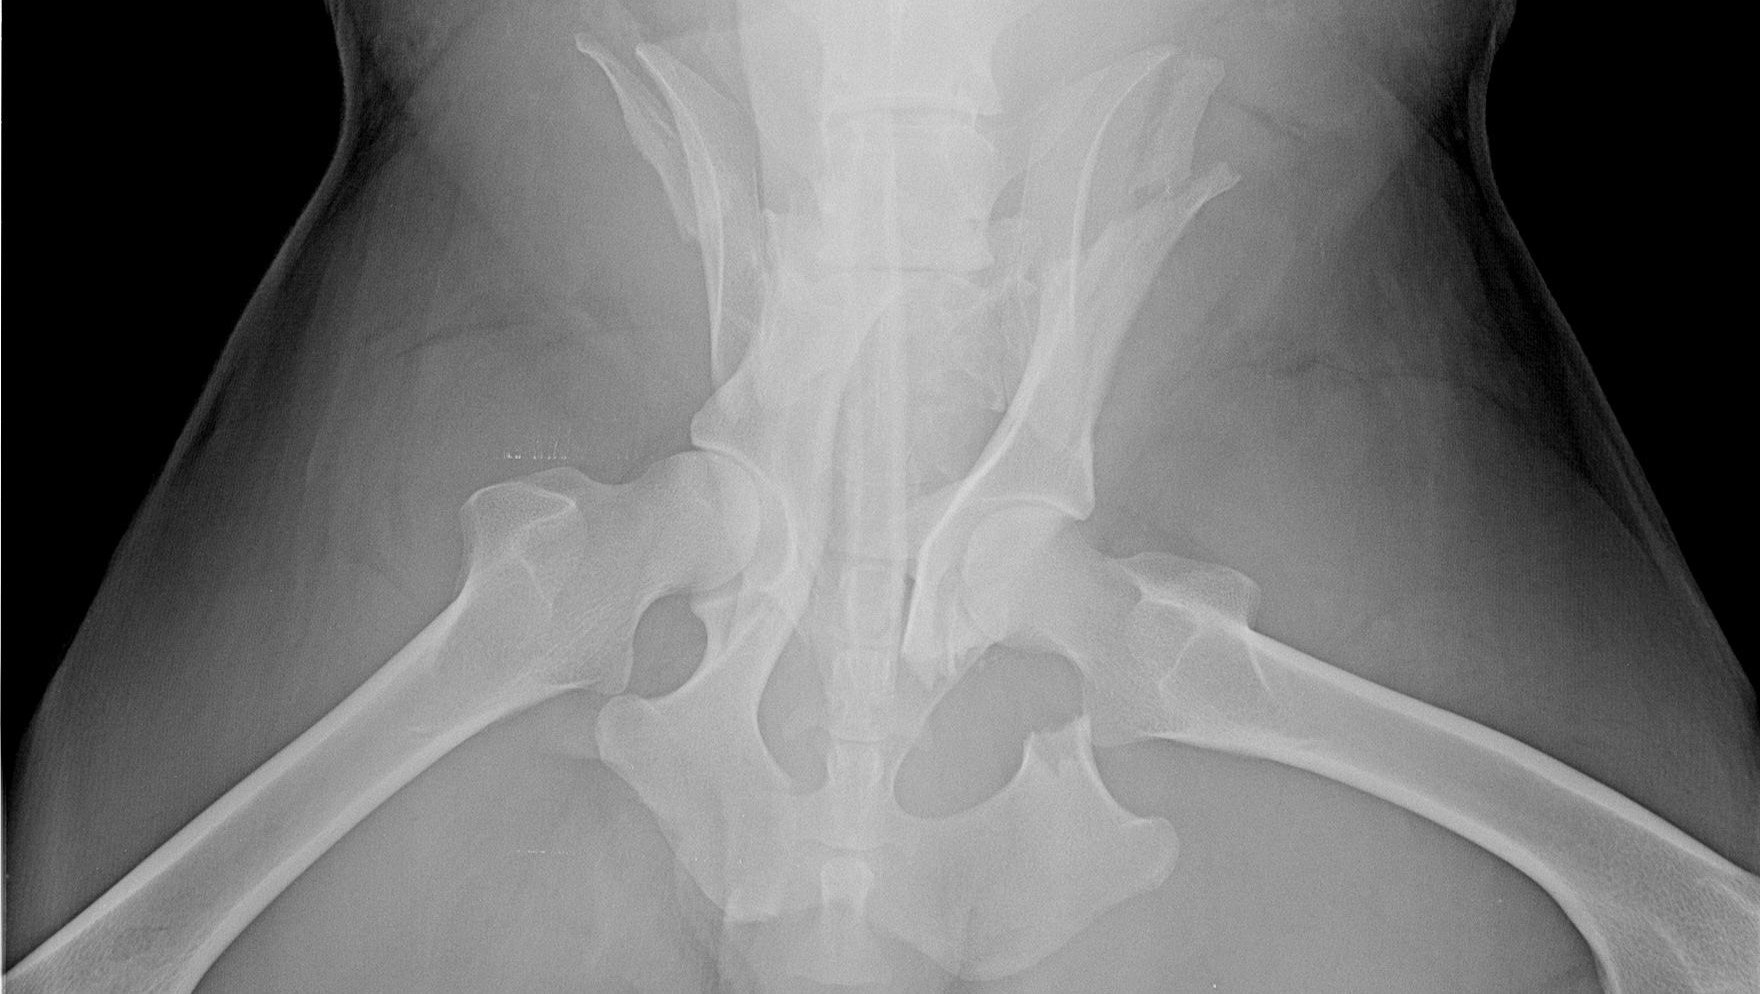

Bran, così lo abbiamo chiamato, è un lupo appenninico maschio vittima di un incidente stradale. Dopo averlo recuperato abbiamo tempestivamente trasportato l'animale al pronto soccorso veterinario dell'Università di Perugia per una prima stabilizzazione e per i primi accertamenti. Le radiografie hanno confermato i nostri timori. Una frattura bilaterale del bacino ed una fissurazione in una vertebra hanno compromesso non solo la funzionalità degli arti posteriori, ma anche quella della vescica e del basso tratto intestinale.